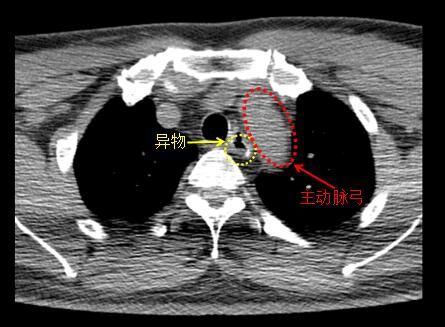

ct显示,异物紧邻主动脉弓。

“异物卡在食道的第三个狭窄处,毗邻主动脉弓,并有两个锋利的尖角,如果患者再次吞东西想把异物压下去,很可能导致异物移位,尖角刺破主动脉弓,导致大出血甚至危及生命”,周建波主任医师表示,食道异物是耳鼻喉科常见急症,仅最近半个月,耳鼻咽喉头颈外一科就收治食道异物患者近10例,其中多数是儿童和老年人,还有醉酒后误吞牙签、金属拉环等异物的。其中,低龄儿童通常是好奇心作祟将异物放入口中,误吞小玩具、硬币、纽扣、笔套等;老年人则多是因为吞咽功能退化、缺牙等原因导致囫囵吞咽,常见的异物有鱼骨、鱼刺、假牙等。